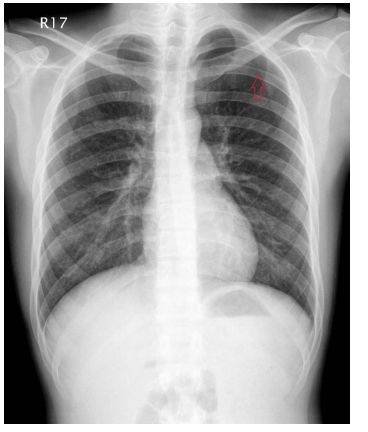

7. 病人58歲婦女,主訴運動性呼吸困難、體重一星期間從84公斤增加至87公斤,雙腳水腫有一週之久,步履難行,初步檢查呈現心臟擴大,乃前往醫學中心診療,在急診初步檢查Chest X-ray、心臟超音波和心電圖(如圖),旋即住院。病人七年前有左乳癌經切除手術,至今並未完全緩解。病人近五年來,有高血壓及糖尿病,都藥物治療中。生命徵象:T: 36.2°C,P:81/min,R:20/min,BP:150/84mmHg,Pain score:0。病史詢問及身體理學檢查,請問下列何組心血管病理學檢查(Cardiovascular approach),是您應該觀察標的? (1) 消沈的S1 and /or S2 (2) S3 and S4 (3) Pericardial friction (4) Mid-systolic murmur and pansystolic murmur (5) Kussmaul sign (6) Pulsating congestive liver

(A)(1)+(2)+(3)(B) (2)+(4)+(6)(C) (1)+(3)+(5)(D) (4)+(5)+(6)(E) (3)+(4)+(5)